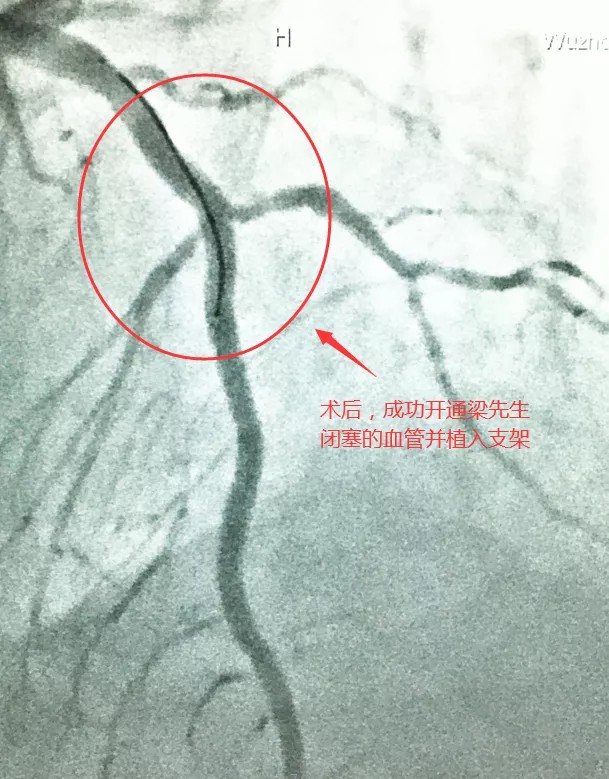

以往该类手术需到省级医疗机构或邀请专家协助,考虑到梁先生病情危重、经济困难,经家属同意,决定在我院做手术。3月20日,心血管内科团队历经约4小时完成了手术。看到梁先生术后逐渐恢复,大家都很欣慰。